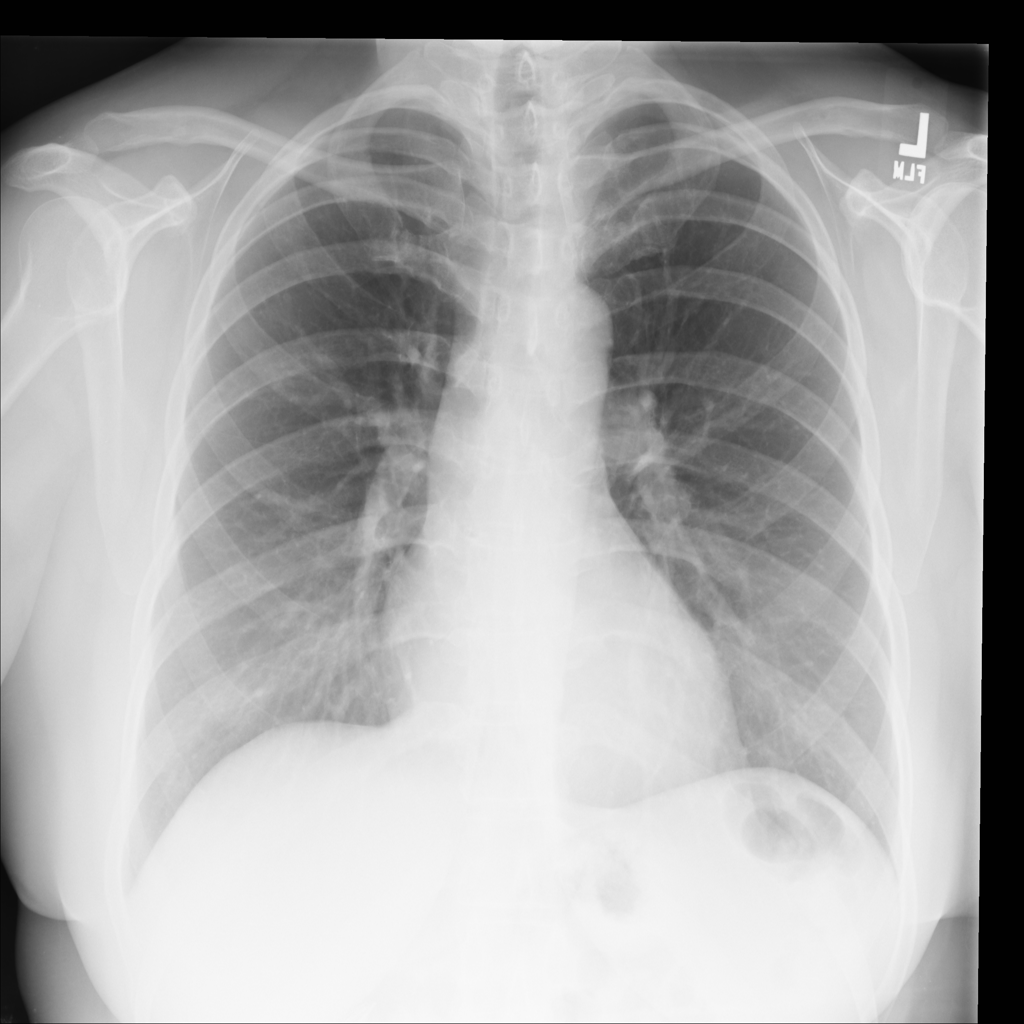

PAT-E828 · IMG-004Edema

PAT-E828 · IMG-004

AP